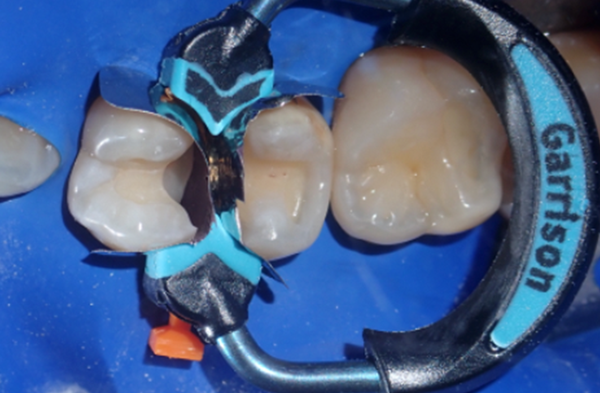

True Dental Dam (Clinician's Choice) was placed to isolate the operative field (Fig. 2). Proper  Isolation remains a cornerstone of adhesive dentistry. It protects the field from contamination with saliva, blood, and moisture, which can significantly compromise the integrity of the adhesive interface. Additionally, a rubber dam improves visibility and access, allowing for precise technique execution and patient safety.

An important clinical tip is to use rubber dam clamps with floss ligatures and WedgeGuards (Triodent) during interproximal preparation to ensure secure and effective isolation around posterior teeth as well as protecting the adjacent teeth from inadvertent damage (Fig 2).

FIG. 2

A rubber dam ensures a dry field, preventing

contamination and improving visibility during the

procedure.

In this case, both teeth were prepped, and the Quad System was placed to ensure stable contact creation during the restoration process. Anatomically shaped wedges and separating rings were inserted to achieve optimal band adaptation and gingival seal (Fig. 5 & 6).

FIG. 5

FIG. 6

Simultaneous placement facilitates the restoration of back-to-back

Class II lesions with proper contact and contour.